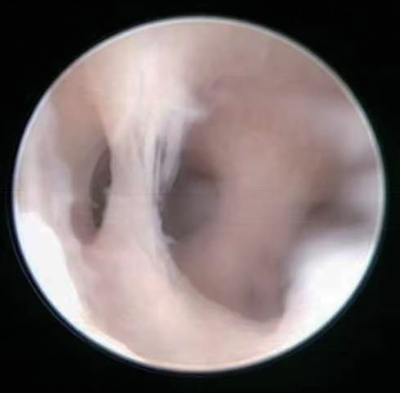

4)子宫腔粘连:按部位分为周围型和中央型子宫腔粘连;按性质分为内膜性、纤维肌性和结缔组织性子宫腔粘连;按严重程度分为轻度、中度和重度子宫腔粘连等(图3-12)。